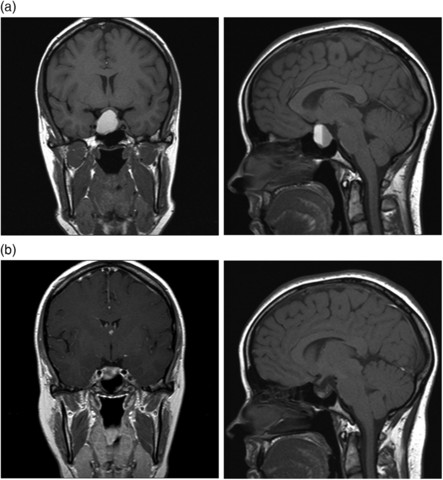

At the age of 10 I was diagnosed with a tumor inside of my sinus cavities. I had major head surgery to remove tumor. My mother expected me to be the tough little girl she had raised me to be, but I was very scared. My siblings and extended family were all very nervous for me. Thankfully I was fine and my tumor was benign .

I was diagnosed with second tumor, this time a pituitary tumor near my brain. I also found out that this is what had been causing infertility issues after trying to conceive baby for more than one year. My mother was really scared and as always expected me to pray and ask God to help me heal fast. I did not do much praying but I did start living a healthier life. My whole family was very attentive and supportive trough this tough time.